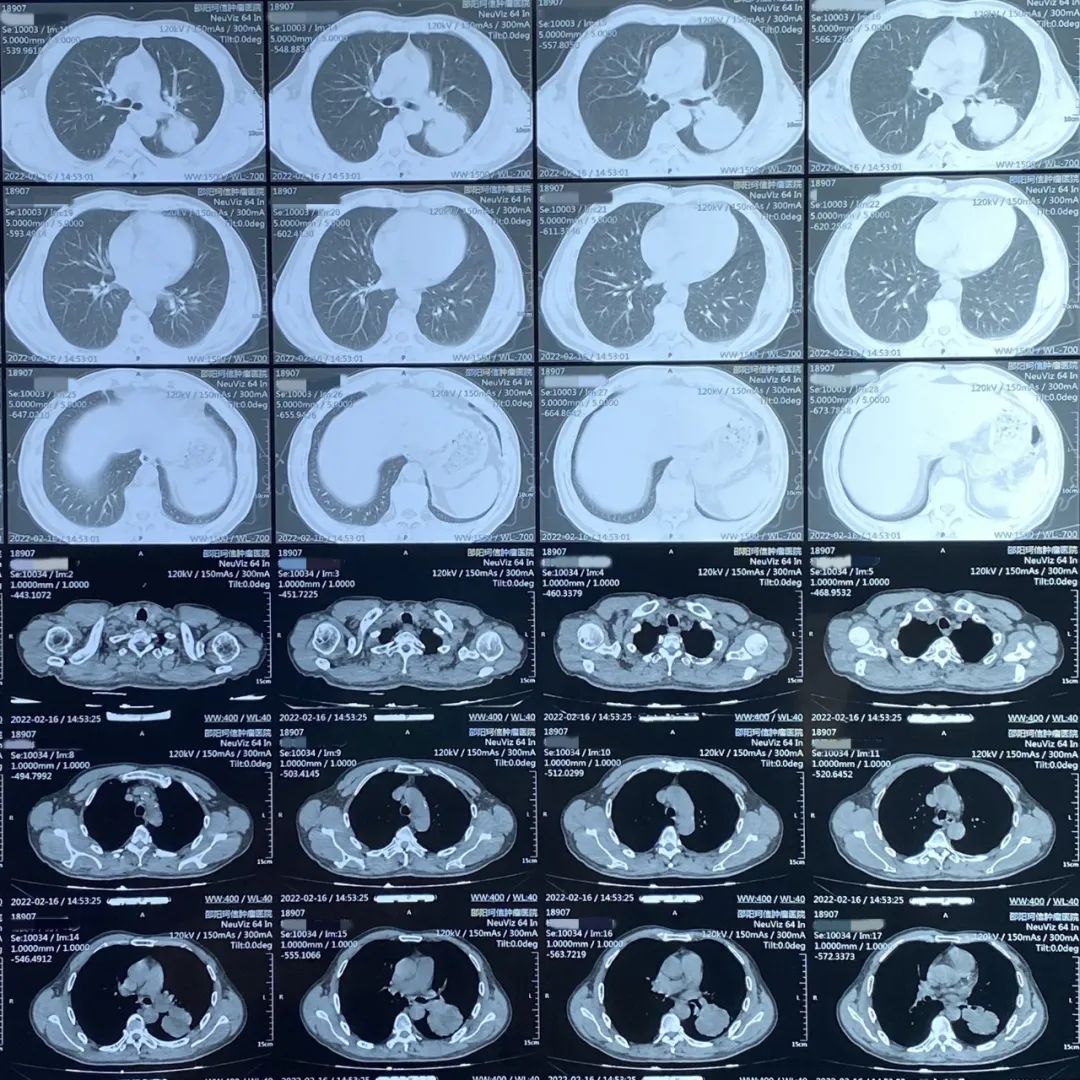

患者:男性,61岁,肺部肿瘤

患者因经常出现咳嗽、胸闷、气喘等症状入院检查,经CT检查所示左肺有占位,病理活检确诊为肺部肿瘤。

肺部CT诊断